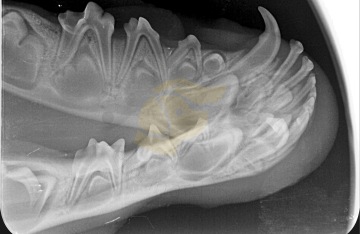

Intraorální rentgen – když zub není vidět

V případech, kdy některý zub není viditelný, ale není jasné, zda skutečně chybí, nebo je pouze neprořezaný, se používá intraorální rentgen. Tento typ snímkování umožňuje zjistit, zda se zub nachází v čelisti, ale z nějakého důvodu neprorazil dáseň (např. je impaktovaný nebo retenovaný).

Rentgen pomáhá určit:

Přítomnost zubu v čelisti.

Genetické chybění zubu (nezaložen).

Zda byl zub extrahován nebo ztracen v důsledku úrazu či nemoci.

Intraorální rentgen se provádí nejčastěji v sedaci nebo krátké anestezii, protože pes musí během zákroku zůstat zcela v klidu. Je to neinvazivní a velmi přesný způsob, jak doložit plnochrupost i v nejasných případech.